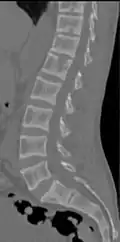

![CT scan of the same case.[18]](./_assets_/CT_of_rugger-jersey_spine_of_renal_osteodystrophy.jpg) CT scan of the same case.[18] CT scan of the same case.[18]